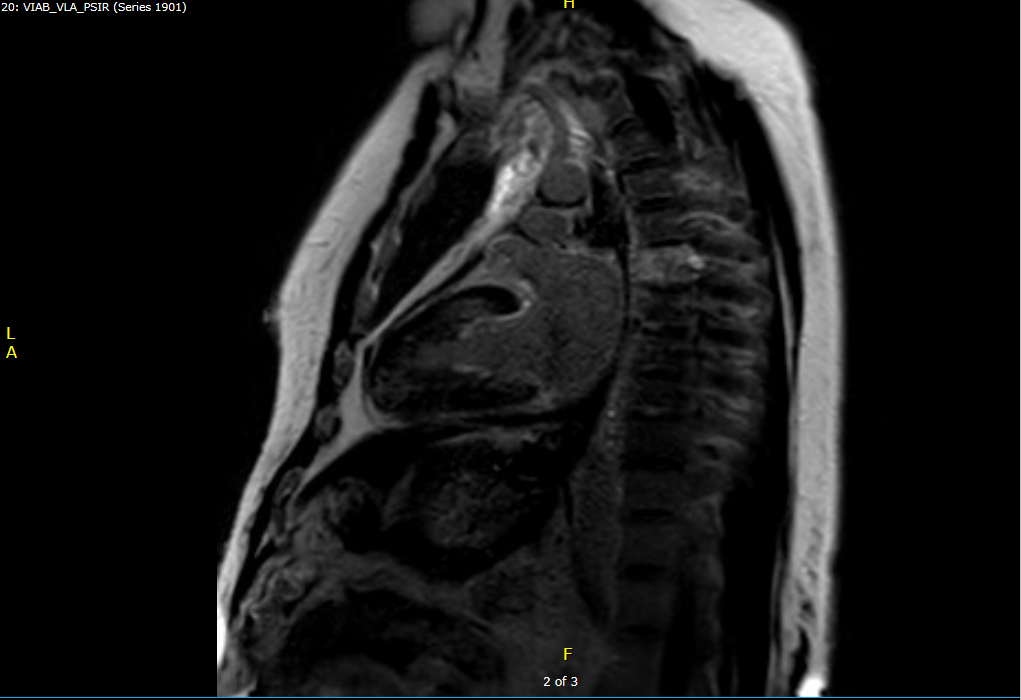

Cardiac MRI: Diffuse circumferential pericardial thickening. No increased pericardial enhancement. No pericardial delayed enhancement. Features of constriction are present with a mild septal bounce, mild conical deformity, diastolic restraint, and dilation of the suprahepatic IVC.

Figure 2: PSIR MRI showing no pericardial late gadolinium enhancement (LGE)